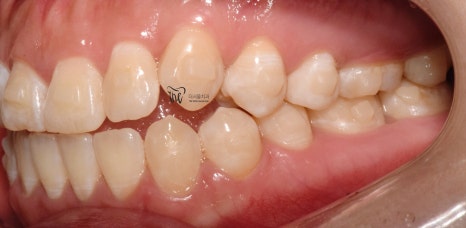

『치료 종료』

그리고, 다른 환자들과는 다르게

정기검진을 할 필요가 없었죠?

매일 보니깐요.

즉, 저와 늘상 가깝게 지내면서 치열의

변화를 같이 지켜봤으며 인비절라인

치아교정 치료를 이어나간 결과

이제 윗니가 아랫니를 겹치게 덮는 모양이

나오게 되면서 치료를 끝마치게 되었네요.

물론, 해당 교합관계는 재발이 잘 되기 때문에

시간이 오래 흘렀을 때도, 꾸준히 검진을

받으면서 관리를 받아야 됩니다.

그러면서, 어느 단계에서부터 턱관절 통증 및

뻐근함이 거의 다 사라졌다는..

이것은, 두마리 토끼를 같이 잡았다.^^

치료 기간 2021.01.03 ~ 2022.05.01